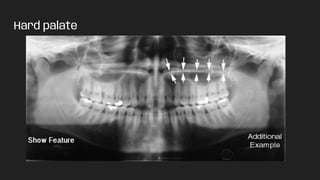

● Hard palate

Hard palate